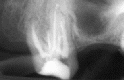

If you are suffering from a tooth infection caused by decay or injury, you may be in need of a root canal. In our Santa Monica office, we will work with you to discuss the root canal treatment and ensure that your procedure is painless and effective, leaving you with an improved, healthy smile after just one visit.